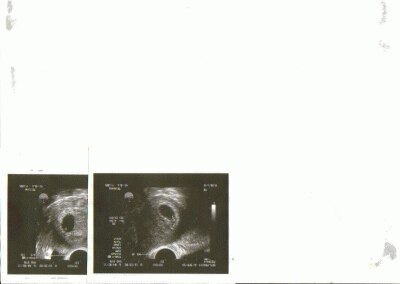

Will euch nicht weh tun, aber wir sind ja, wie es den meisten bekannt ist, durch Clomifenbehandlung schwanger geworden ( Ges. 9 Monate in Beahndlung ) und jetzt bekommen wir Zwilli´s... Komme grad vom Arzt, Foto anbei !! Und jetzt drücke ich Euch allen so dermaßen fest die Daumen, dass es weh tut

Bild zu Falls es euch interessiert... - Kinderwunschbehandlung

Hallo...na dann alles Gute..super Zwillinge. Habe Fotos angeschaut, dass ist echt toll! Hoffe bei uns klappts auch! Werden sicher 2 Eiige...na dann eine tolle Schwangerschaft. Habe jetzt nicht richtig mitbekommen...du hattest keine ICSI?